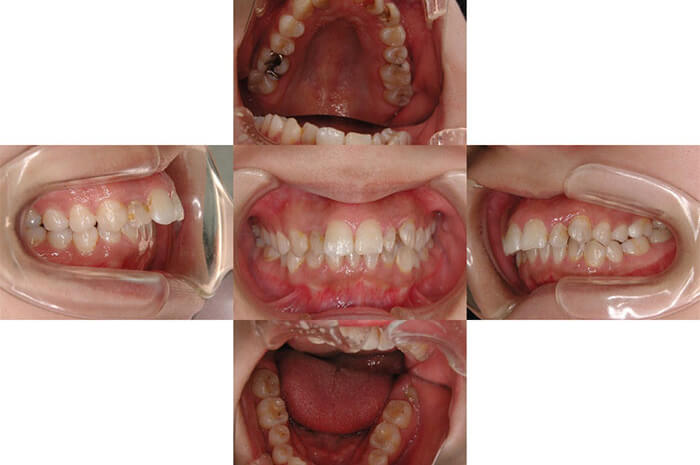

症例紹介

右上2、左上2、3は神経に達する大きなむし歯だったため、神経を取る処置を行っています。

右上2、左上2、3はフェルル(※)が不足しているため、挺出(ていしゅつ:引っ張り出す処置)を同時に行っています。この段階では、辺縁歯肉のラインがそろっていません。

辺縁歯肉のラインを整え、フェルル確保のため歯冠長延長術(歯冠がほとんどなくなってしまった場合に、歯ぐきの位置を下げて歯の縁を出す外科処置)も行っています。

プロビジョナル(最終的な人工歯を装着する前に装着する仮歯)で、辺縁歯肉のラインを整えます。

治療完了です。

臼歯の症例

施術前

施術後